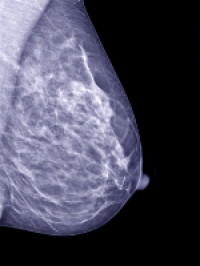

An international team of researchers has identified several risk factors for persistent pain after breast cancer surgery; these include younger age, radiation therapy and removal of lymph nodes under the arm (axillary lymph node dissection), in a new study published in the Canadian Medical Association Journal.

To understand the factors associated with chronic postsurgical pain, researchers from Canada, China, Brazil, Spain and Ireland conducted a systematic review of 30 studies with data on 19,813 patients who underwent surgery for breast cancer.

The largest risk factor was axillary lymph node dissection, which was associated with a 21% increase in risk of pain.

This procedure is often done during a partial or full mastectomy.